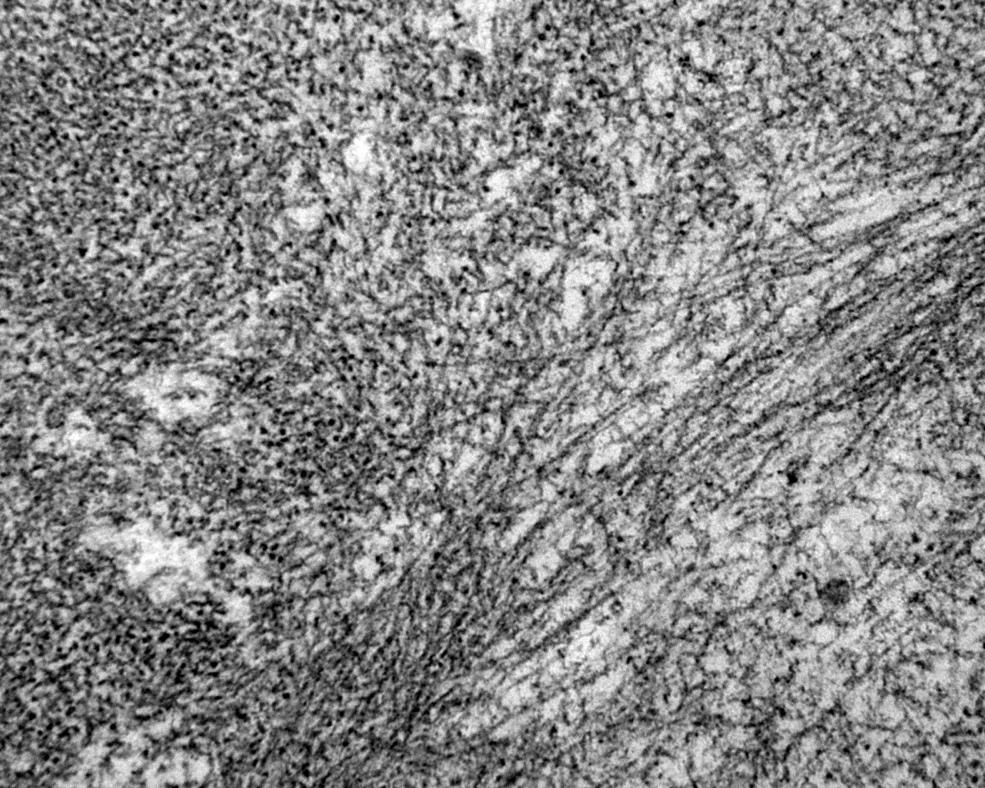

1.3 Definisjon og karakteristika

Figur 1. Amyloidfibriller i nyrebiopsi (elektronmikroskopi, x 40 000)

2. Patogenese

Hvilke mekanismer som er involvert i dannelsen av amyloide fibriller er ikke kjent i detalj, men in vitro studier har vist at fibrilledannelsen foregår i flere trinn. Isolerte amyloide fibriller har helt spesielle egenskaper som er forskjellige fra andre typer fibriller. Amyloide fibriller er i hovedregel ikke forgrenede. Fibrillenes lengde kan variere; mens fibrillediameteren (tykkelsen) er 8-10 nm (se Figur 1 ovenfor).

Elektronmikroskopi og røntgenkrystallografistudier av amyloide fibriller viser at de har en karakteristisk beta-plate struktur som benevnes som «cross-beta» (36).

3.1.3 Verifisering av fibriller med elektronmikroskopi

Ved sparsomme avleiringer og ved usikkert resultat av kongorød farging kan elektronmikroskopi brukes for å verifisere amyloid ved påvisning av typisk fibrillestruktur med ikke-forgrenede fibriller på 7-12 nm. Imidlertid er det kun små vevsfragmenter som kan undersøkes med elektronmikroskopi, slik at metoden brukes sjeldent for diagnostikk av amyloid. Elektronmikroskopi er lite egnet til typing av amyloid, men i tvilstilfeller kan immunogull undersøkelse (immunelektronmikroskopi) brukes for å bekrefte f.eks. AL-amyloidose.